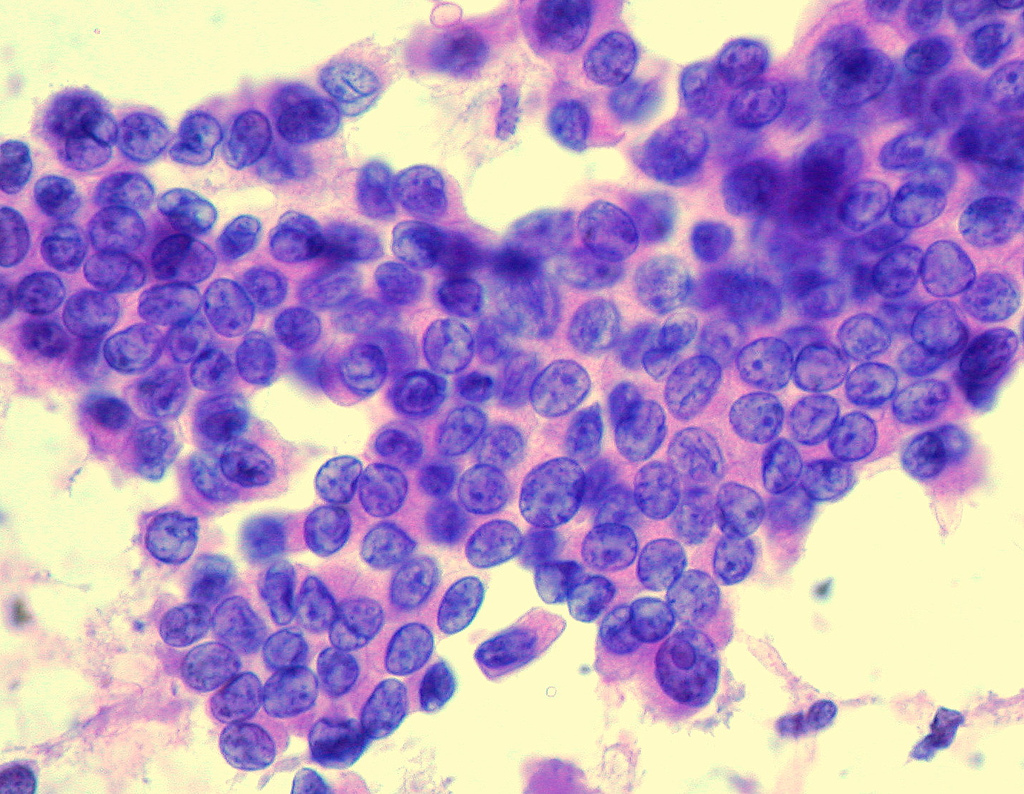

Papillary Thyroid Cancer

Papillary thyroid cancer is not comparable tumor with the superficial layer of the dermis raised into papillae and follicular structures that is characterized by overlaying cell’s genetic material (nuclei) that have a GGA (ground glass appearance or a shadowy pattern) and longitudinal long narrow channels with invaginations of cytoplasm into the nuclei.

Encapsulated and contained, deep narrow-mouthed depression or follicles, tall cell, a stack of columns in an epithelial layer (columnar-cell), clear cell and scatter pathological hardening of tissue (sclerosing) carcinomas are recognized as distinctively different histomorphologic phenotypes of a particular neoplasm (histologic variants); they are classified as papillary carcinomas because of their characteristics.

Papillary Thyroid Cancer is the most common form of cancers of the thyroid – and arises from the thyroid epithelial cells or thyrocytes, which produce and store triiodothyronine (T3) and thyroxine (T4) – the thyroid hormones. Cancer of papillary thyroid usually affects people aged thirty to fifty.

The tumor is unencapsulated and multicentric in twenty to eighty percent of patients.

Usually lymphatic route of spread

Distant metastasis to lungs

Iodine excess

- Occurs between ages – 30 through 50

- More common in women than men by three to one ratio

- Prognosis (the likely course of a medical condition) directly related to tumor size [less than one and a half cm (half an inch)]

- Accounts for eighty five percent of thyroid cancers

- X-ray exposure or radiation exposure can be causative factors

- Spread to lymph nodes of the neck present in up to fifty percent of cases

- Cancer spread to lungs or bones is very rare

- Curative possibility is very high (near hundred percent for small papillary cancers in young patients)

- Overall excellent prognosis with a life expectancy similar to general population: five – year, ten year and twenty – year survival is ninety six percent, ninety three percent and greater than ninety percent respectively

- Disease specific survival is close to hundred percent if under age twenty

- Regional nodal involvement does NOT affect likely outcome

- Five- twenty percent have local relapses, ten – fifteen percent have distant metastases (cancer that has spread from the original tumor to distant lymph nodes), (lung, bones, CNS)

- Unfavorable prognostic Indication of a disease recognized by the ATA – American Thyroid Association Management Guidelines include

- Intermediate risk: tall cell / hobnail / uniform ovoid / elongated nuclei perpendicular to basement membrane – columnar cell variant (PTC‐CCV), vascular invasion ((VI), which is known as blood and/or lymph vessel invasion (LBVI), pN1 disease with greater than five positive small glands that filter lymph (lymph nodes) and the largest metastatic focus smaller than three cm in greatest dimension, microscopic extrathyroidal extension (perithyroidal fibro adipose tissue)

- Increased risk: gross extrathyroidal extension (ETE – extension of the primary tumor outside of the thyroid capsule – larynx, vasculature, esophagus and beyond), incomplete tumor resection (poor prognostic factors in thyroid cancer patients), distant metastasis (cancer that has spread from the original tumor to distant lymph nodes), pN1 with a metastatic focus ≥ 3 cm in largest dimension

- Elder age at diagnosis (≥ fifty-five years) is a poor prognostic factor

- Succession to poorly differentiated thyroid carcinoma or (ATC) – anaplastic thyroid carcinoma characterized by growth of cells that is uncontrollable in the thyroid gland and infers a poor prognosis

[4]Image credit: https://commons.wikimedia.org/wiki/File:Papillary_Carcinoma_of_the_Thyroid.jpg